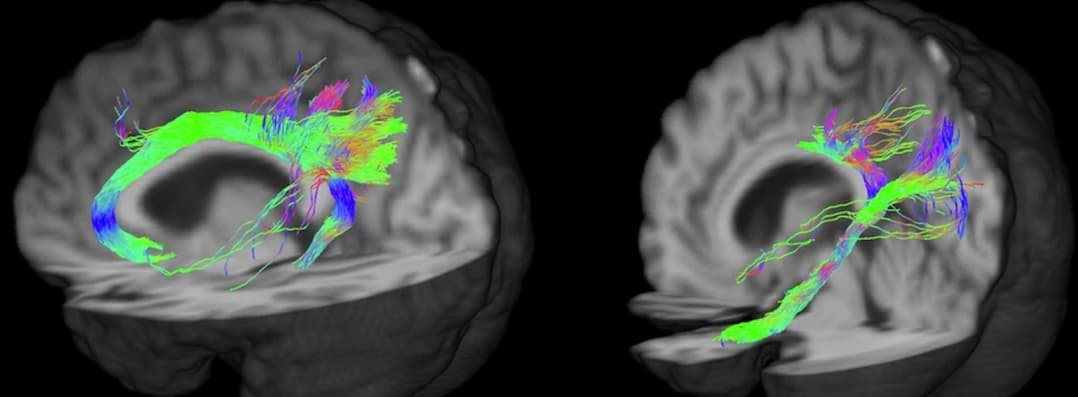

La tractographie par IRM devient un outil pertinent pour évaluer les flux dans les faisceaux de fibres cérébrales. Une étude italienne publiée dans la Revue European Radiology explore la complexité du faisceau cingulaire par tractographie probabiliste et expérimente plusieurs protocoles d’acquisitio...